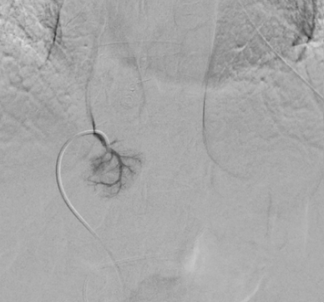

Atraumatic Pulmonary Valve Crossing to Enable Successful Embolization of Multiple Pulmonary Arteriovenous Malformations after Failed Attempts

Symeon Lechareas, Melpomeni Spyropou;ou, Marianna Vlychou, Georgios Papageorgiou

1-6